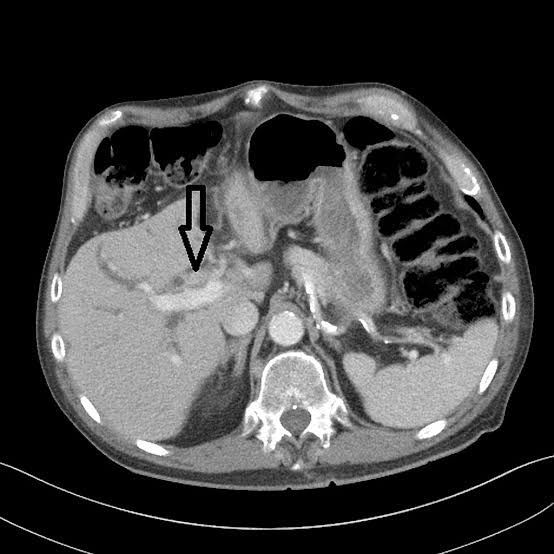

Hilar carcinoma occurs at the confluent of left and right hepatic bile ducts. Many conditions such as primary sclerosing cholangitis, choledochal cysts, clonorchis sinensis infections, and exposure to nitrosamine and asbestos can predispose to this type of malignancy. Reference: https://en.m.wikipedia.org/wiki/Klatskin_tumor Image via: https://radiopaedia.org/cases/klatskin-tumour-1?lang=gb